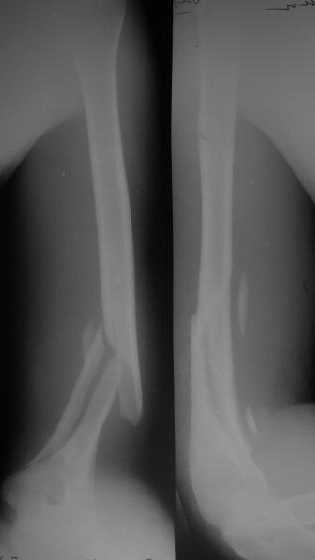

Мы в последние годы все еще используем для переломов такой

локализации эластичные титановые стержни (по мотивам ярославских

разработок, Зверева-Ключевского). Такой стержень можно вводить не

через сухожилие надостной мышцы, а дистальнее.

Снимки до, через 1 и 2 мес. после синтеза.